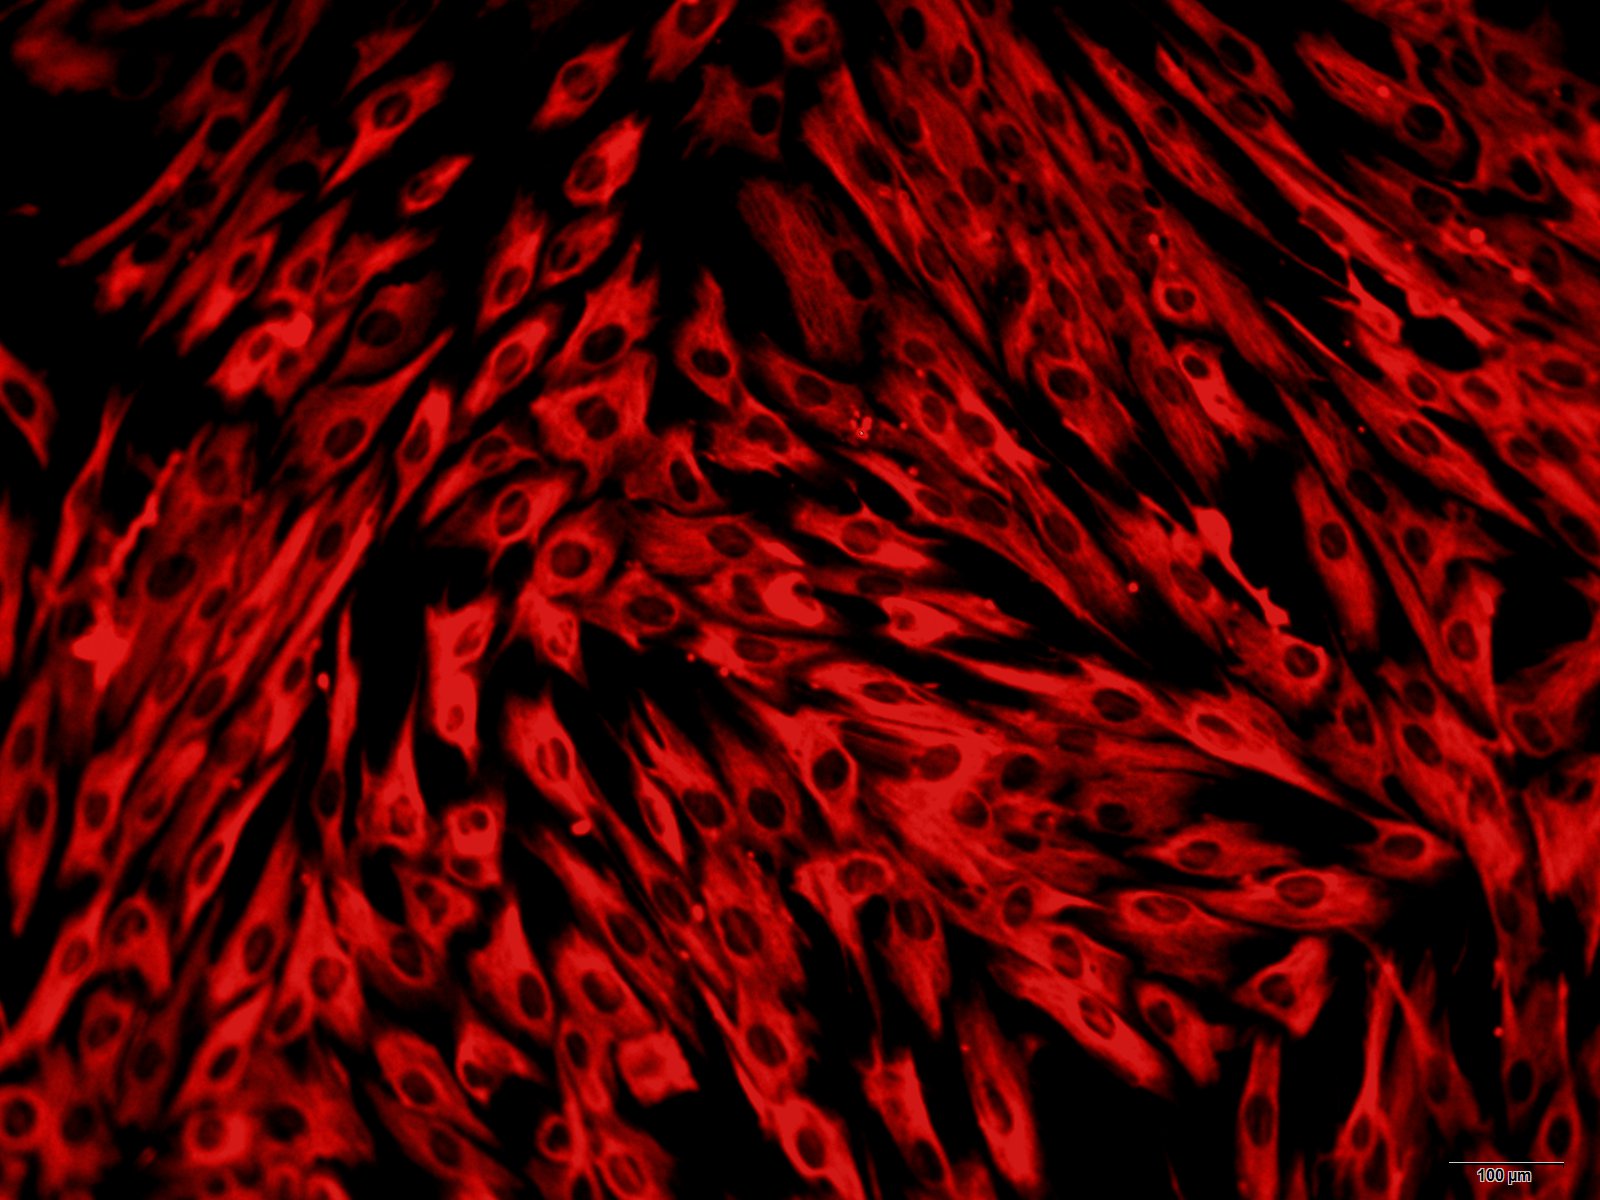

人直肠癌组织源细胞

本公司生产的人直肠癌癌组织源细胞采用酶解法制备而来,细胞总量约为5×105/T25方瓶,细胞纯度可达90%以上,且不含有HIV-1、 HBV、HCV、支原体、细菌、酵母和真菌等。